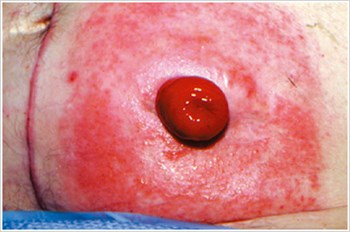

농피증 괴저(Pyoderma Gangrenosum)

설명/원인:

크론병이나 궤양성 대장염과 같은 염증성 장 질환(IBD) 환자에서 흔히 볼 수 있는 염증성 피부 질환.

조짐:

- 불규칙한 모양, 붉은색, 통증, 감염된 궤양, 빨간색에서 보라색으로 말린 가장자리; 다리, 엉덩이, 얼굴, 장루 주위 부위에 나타납니다.